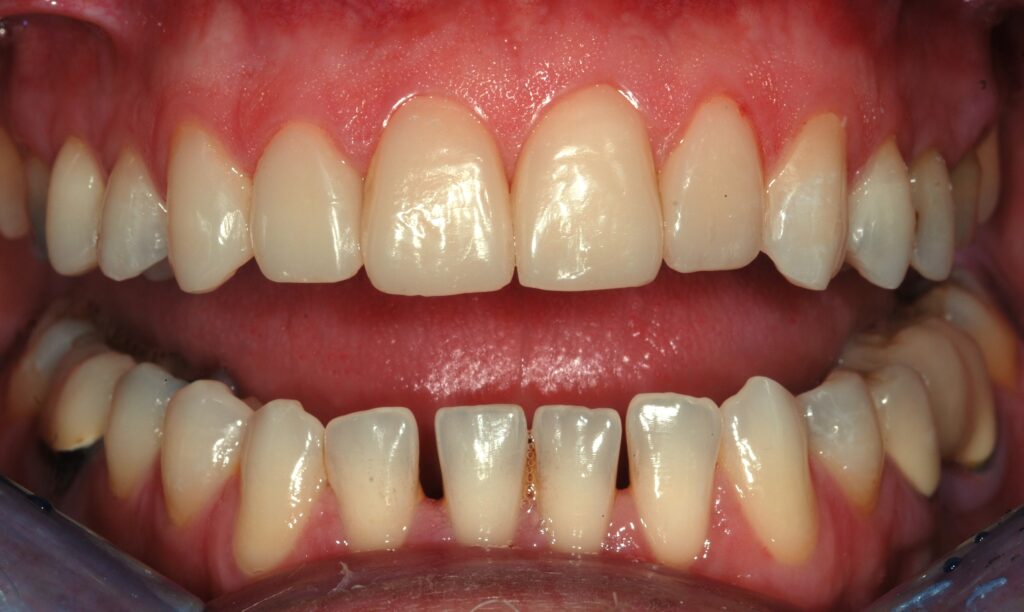

Nell’era dell’odontoiatria conservativa, la sfida è ottenere il massimo risultato estetico con il minimo sacrificio di tessuto dentale sano. In Dentalstyle, abbiamo perfezionato l’adozione della Flow Injection Technique, una metodica rivoluzionaria che permette di trasformare il sorriso dei pazienti in modo rapido, prevedibile e, soprattutto, additivo.

La teoria trova la sua conferma definitiva nella pratica quotidiana del nostro laboratorio. Negli ultimi mesi, abbiamo documentato numerosi casi in cui la Flow Injection Technique ha risolto sfide estetiche complesse con una naturalezza sorprendente.

- Integrazione marginale perfetta: grazie alla precisione millimetrica della nostra mascherina trasparente, la transizione tra dente naturale e restauro è impercettibile, eliminando l’antiestetico “effetto scalino”.

- Morfologia naturale: ogni dettaglio del wax-up, dalle creste marginali alle micro-tessiture superficiali, viene trasferito fedelmente in bocca.

Dalla chiusura dei diastemi al ripristino di intere arcate usurate, i casi trattati da Dentalstyle dimostrano che è possibile coniugare un approccio ultra-conservativo con un’estetica di altissimo livello. Vedere il paziente sorridere con sicurezza, sapendo che i suoi denti sani sono rimasti intatti, è la soddisfazione più grande per il clinico e per noi tecnici.